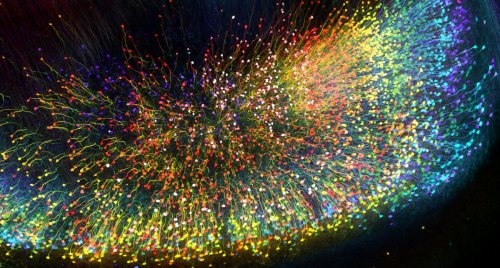

Мозговое вещество трансгенной мыши в 3D